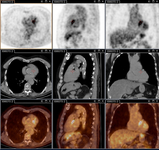

Aneurisma micótico na aorta torácica da febre Q diagnosticado na PET: PET/TC com 18-fluordesoxiglucose. Neste paciente assintomático com história de valva cardíaca e sorologia elevada, a PET permitiu diagnosticar endocardite aórtica na valva nativa com aneurismas micóticos da aorta torácica e lombar

Institut Hospitalo-Universitaire Méditerranée Infection (obtido consentimento do paciente)

Endocardite por febre Q diagnosticada na PET: PET/TC com 18-fluordesoxiglucose. Neste paciente assintomático com história de valva cardíaca e sorologia elevada, a PET permitiu diagnosticar endocardite aórtica na valva nativa com aneurismas micóticos da aorta torácica e lombar

Aneurisma micótico na aorta lombar da febre Q diagnosticado na PET: PET/TC com 18-fluordesoxiglucose. Neste paciente assintomático com história de valva cardíaca e sorologia elevada, a PET permitiu diagnosticar endocardite aórtica na valva nativa com aneurismas micóticos da aorta torácica e lombar